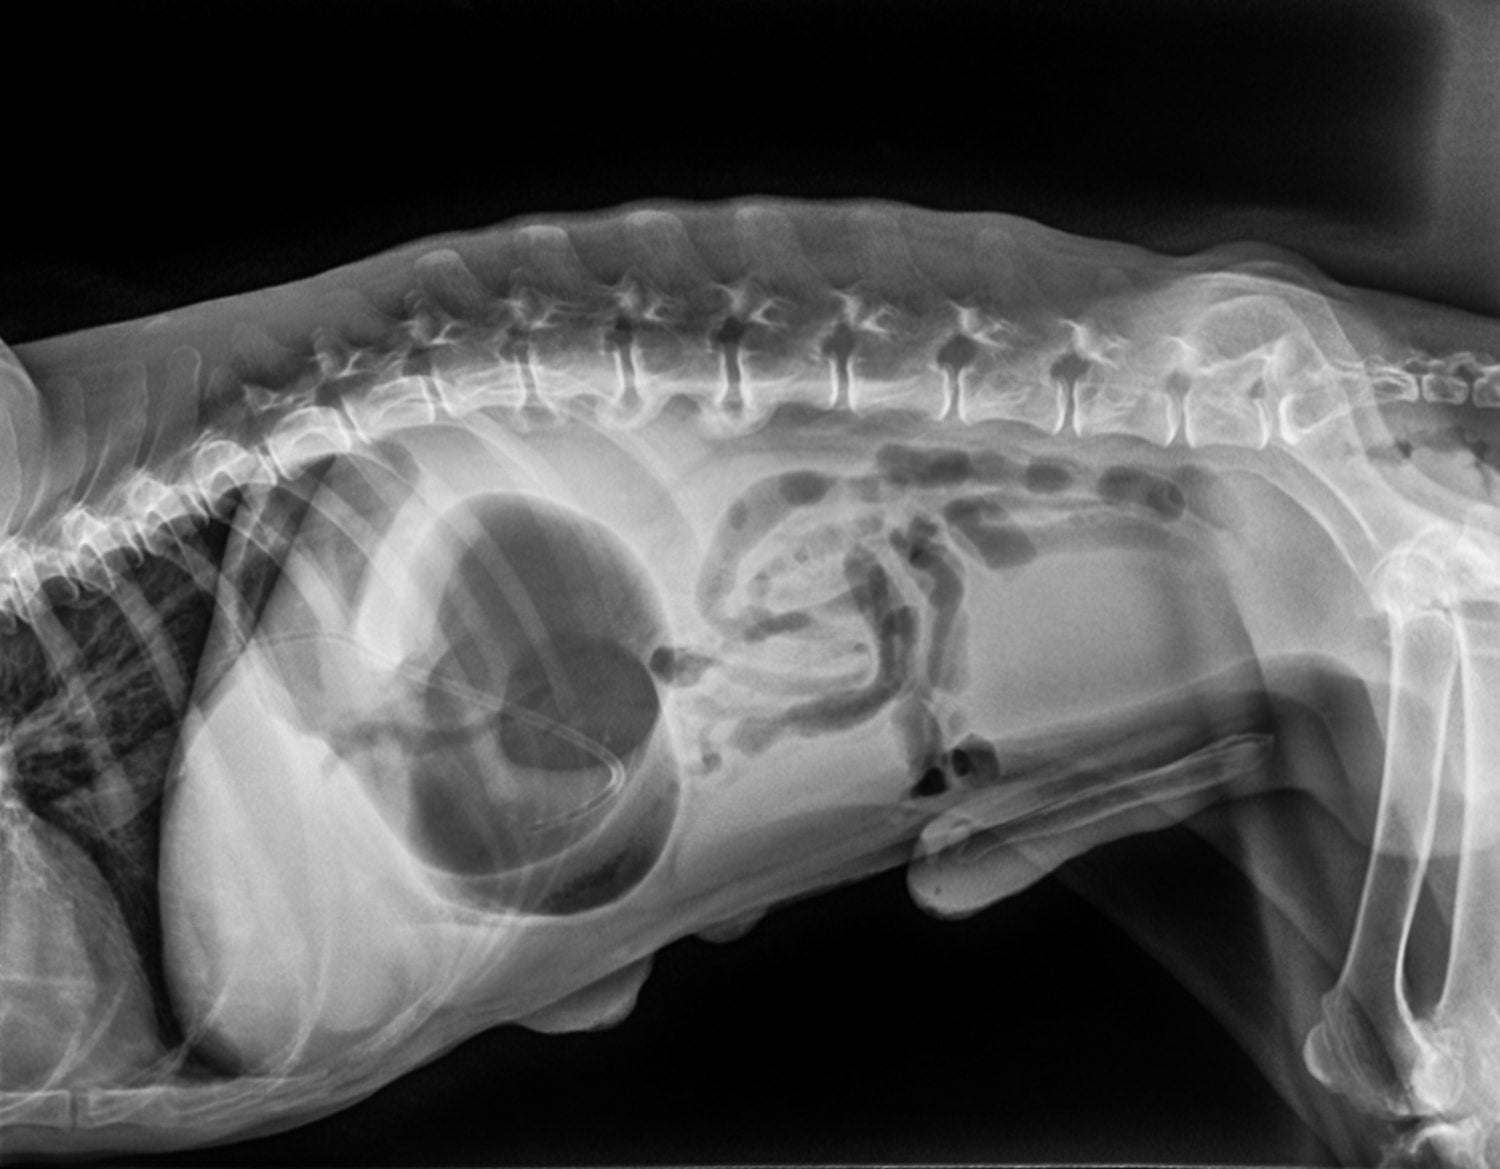

Upon arrival, veterinary surgeons will conduct a physical examination and may perform blood tests to assess your dog's condition. X-rays often reveal the characteristic "double bubble" appearance of a twisted stomach.